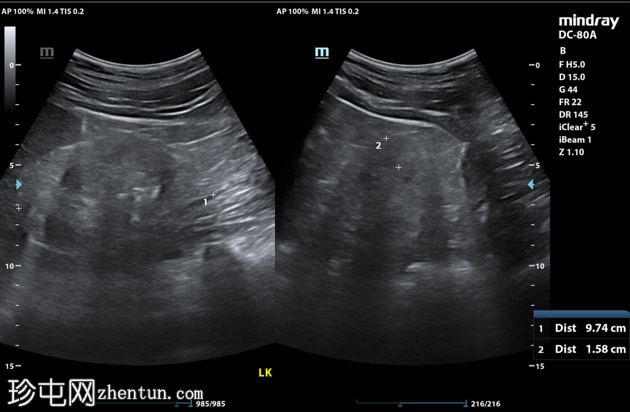

超声检查

左肾

双肾大小正常,回声增强。皮髓质分界清晰。未见局灶性肾实质病变。

左肾未见结石或积水。